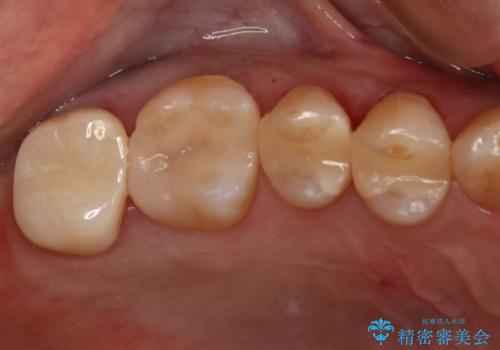

オールセラミッククラウン

金属を一切使わずセラミックのみで構成されており、自然な色調を再現することに長けた被せ物をオールセラミッククラウンといいます。

以前は耐久度(割れにくさ)の点で不安があるといわれていましたが、人工ダイアモンドとも呼ばれる『ジルコニア』の加工技術が向上してきたことにより、より精密で高強度の被せ物が製作されるようになりました。

ジルコニアで補強したベースの上に細かな色調が再現できる陶材を築盛することで周りの歯と調和した色調の被せ物の作製が可能となっています。